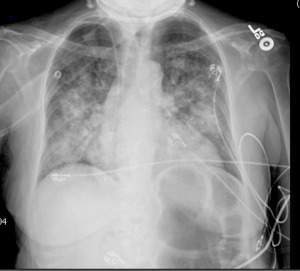

A 62-year-old female was admitted to the general medical department with fever, shortness of breath, chills, and myalgia 18 months after a deceased-donor renal transplant for end-stage renal disease from focal segmental glomerulosclerosis. The patient’s post-transplant course was complicated by gallstone pancreatitis and non-ST elevation myocardial infarction. The patient’s posttransplant immunosuppressive regimen consisted of mycophenolate 360 mg oral tablet two times daily, belatacept 250 mg IV infusion once every 30 days, and prednisone 5 mg tablet daily. The patient had received her last infusion of belatacept nine days prior to the hospital presentation. The patient’s other home medications included aspirin, atorvastatin, isosorbide mononitrate, amlodipine, sacubitril-valsartan, denosumab, pantoprazole, and minoxidil. On presentation, the patient was noted to be febrile with a temperature of 100.8 Fahrenheit, tachycardic at 102 beats per minute, and tachypneic with a respiratory rate of 32 per minute. The patient denied any history of fungal infections or recent travels and was not a resident of the histoplasmosis endemic region. Pertinent physical examination included a toxic-appearing woman in moderate distress and bilateral fine crackles in the lower lobes of the lungs. Initial laboratory workup showed an elevated procalcitonin level, lactate dehydrogenase, and transaminitis. A chest X-ray showed cardiomegaly with bilateral pulmonary infiltrates, as shown in figure 1.